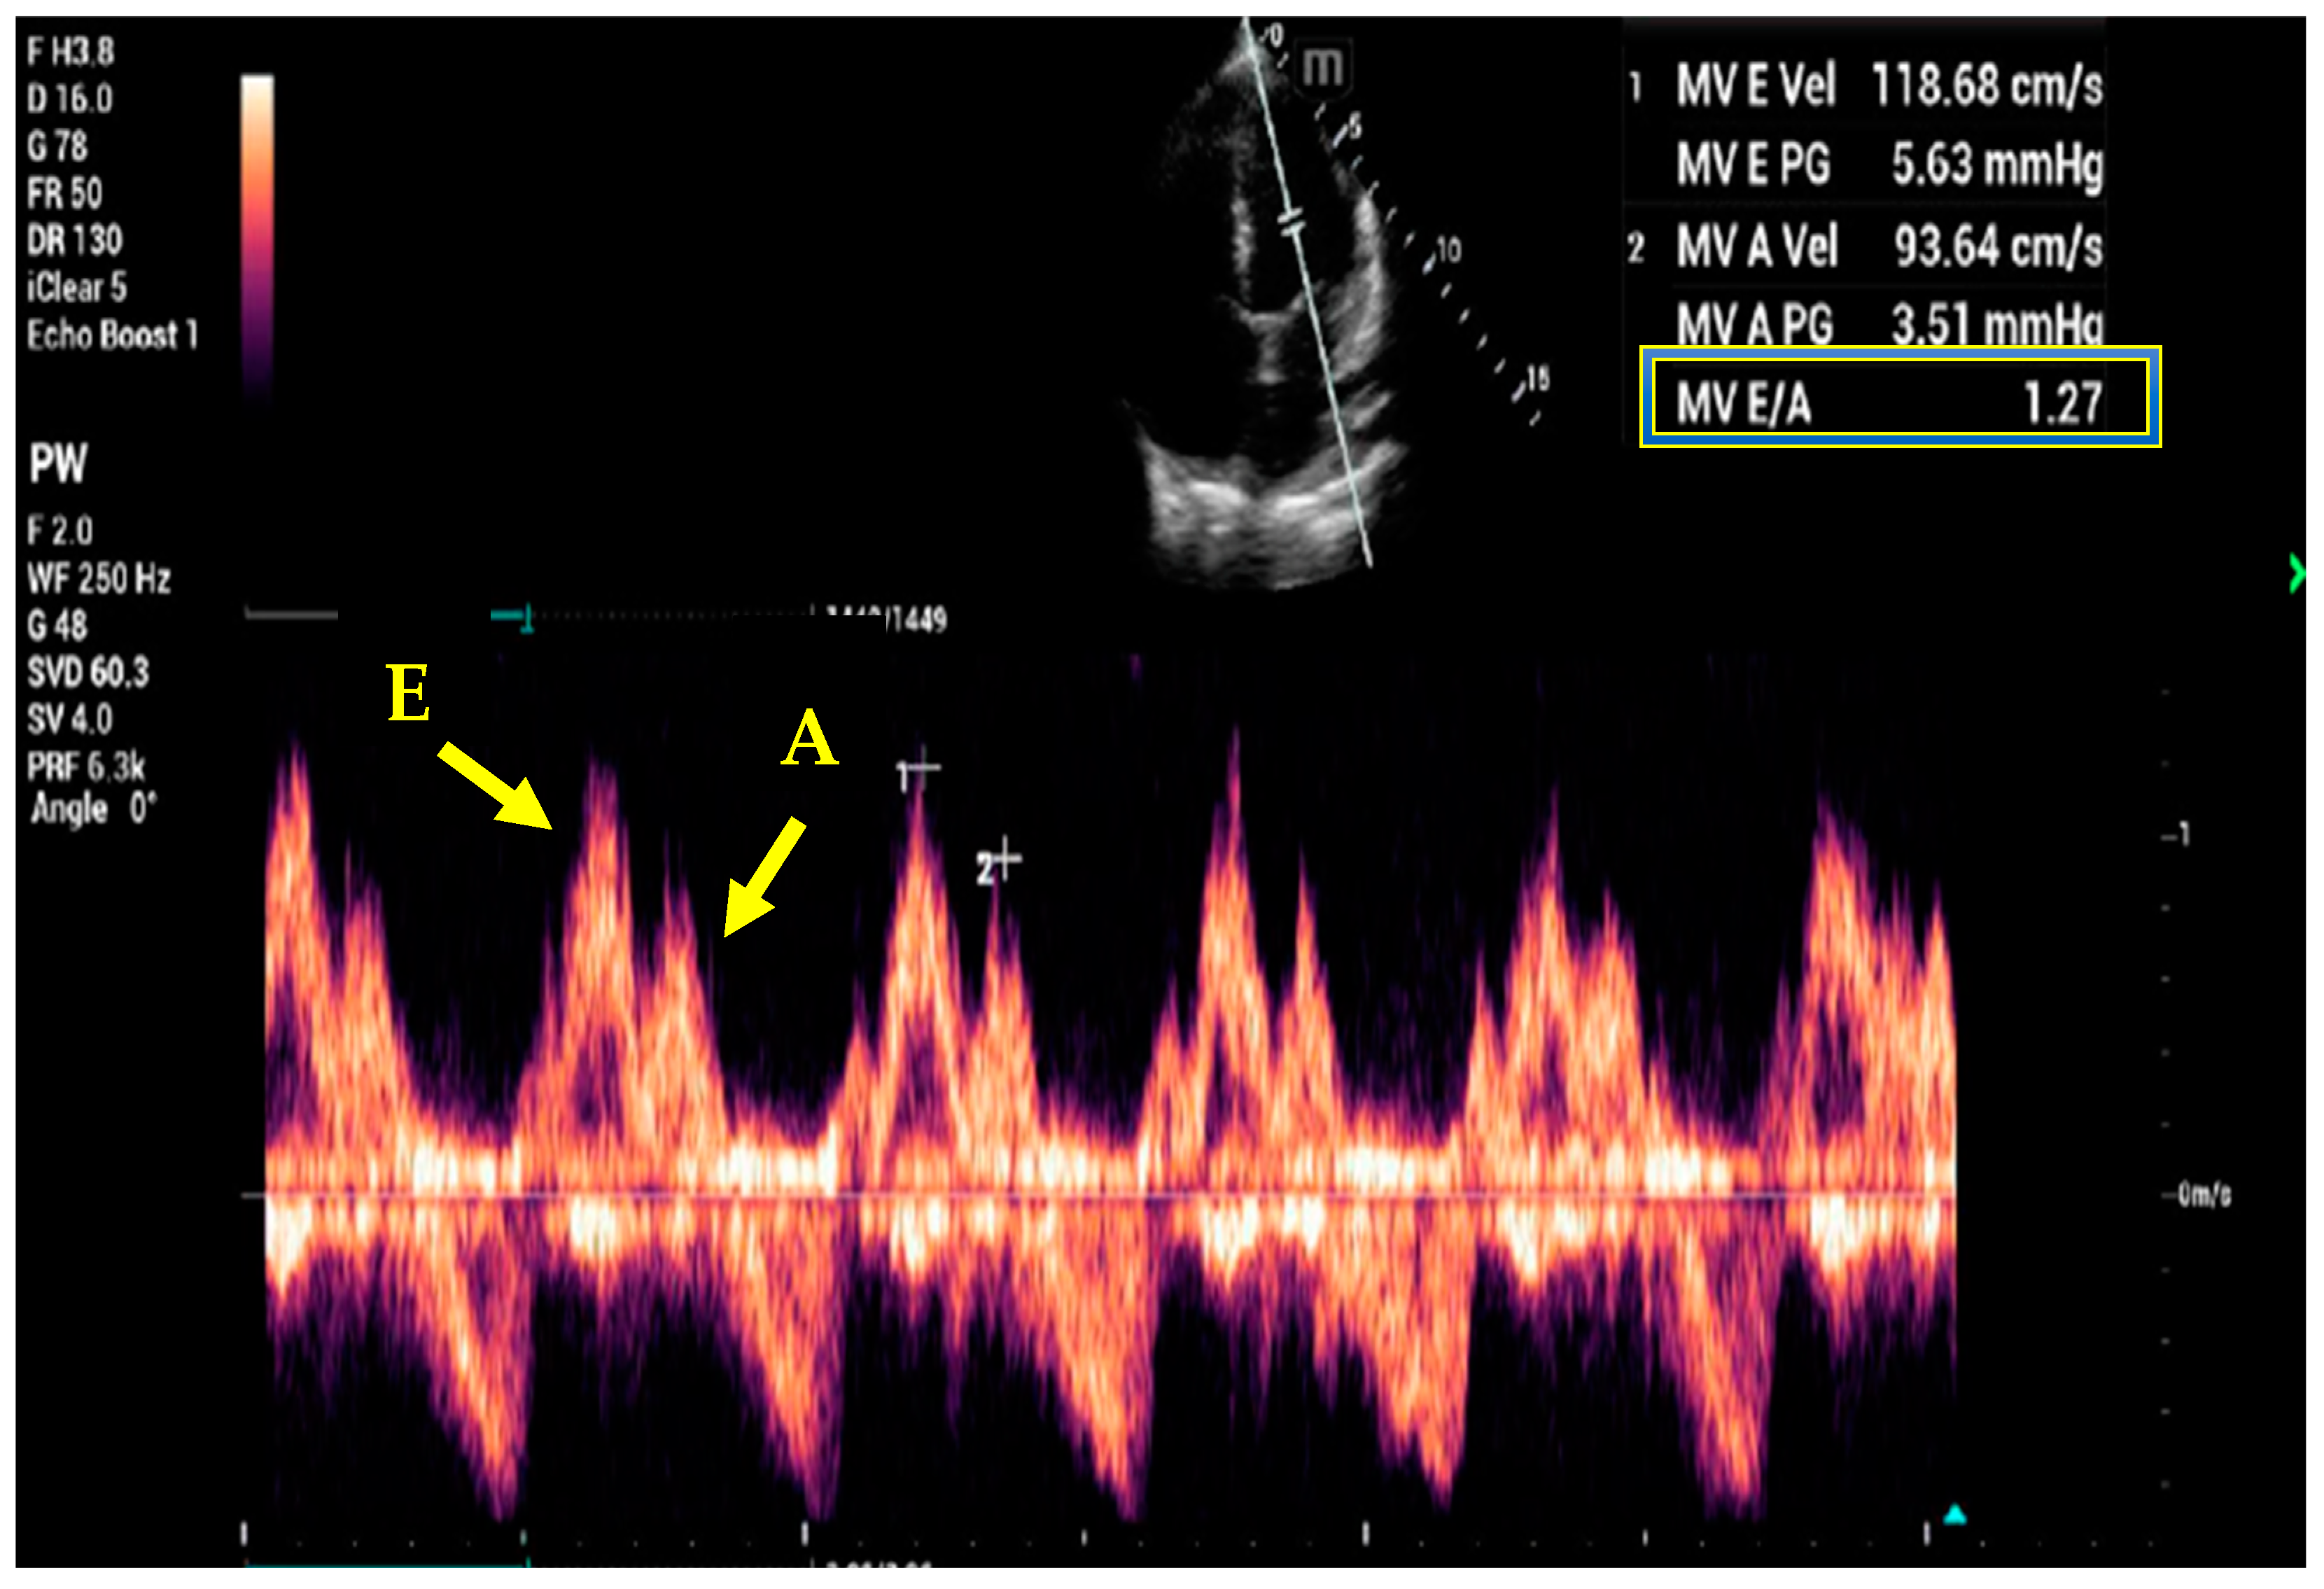

- Kim, J.S.; Yang, J.W.; Yoo, J.S.; Choi, S.O.; Han, B.G. Association between E/e ratio and fluid overload in patients with predialysis chronic kidney disease. PLoS ONE 2017, 12, e0184764. [Google Scholar] [CrossRef] [PubMed]

- Nagueh, S.F.; Middleton, K.J.; Kopelen, H.A.; Zoghbi, W.A.; Quinones, M.A. Doppler tissue imaging: A noninvasive technique for evaluation of left ventricular relaxation and estimation of filling pressures. J. Am. Coll. Cardiol. 1997, 30, 1527–1533. [Google Scholar] [CrossRef]

- Nagueh, S.F.; Smiseth, O.A.; Appleton, C.P.; Byrd, B.F., 3rd; Dokainish, H.; Edvardsen, T.; Flachskampf, F.A.; Gillebert, T.C.; Klein, A.L.; Lancellotti, P.; et al. Recommendations for the Evaluation of Left Ventricular Diastolic Function by Echocardiography: An Update from the American Society of Echocardiography and the European Association of Cardiovascular Imaging. J. Am. Soc. Echocardiogr. 2016, 29, 277–314. [Google Scholar] [CrossRef]